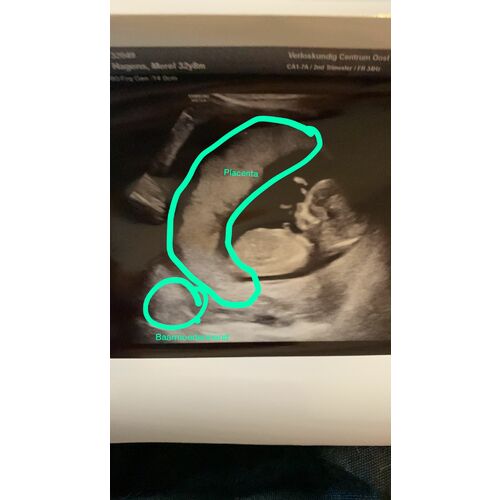

Mijn placenta ligt deelt voor de baarmoedermond. Is meteen gewaarschuwd dat ik sneller bloedingen kan krijgen. Tot nu toe nog niks gehad (27w). Bij week 32 staat een nieuwe echo gepland die moet aantonen of de placenta verschoven is of is blijven zitten en ik dus een keizersnede zal moeten. Maar die kans is blijkbaar maar 2%.

Mocht ik een bloeding krijgen, meteen bellen en dan kan ik komen voor een controle, nog niet nodig gehad.

Als het echt slecht was, had de vk er wel iets van gezegd. Het kan ook dat je baarmoeder ineens hard groeit waardoor de placenta en baarmoedermond over elkaar heen schuren, waardoor je een bloeding hebt. Mijn buik is nog vrij bescheiden en begint nu pas echt met de week te groeien dus wellicht komt het bloeden nog. 脫f omdat het zo langzaam gaat, is er minder schuring en krijg ik geen bloed.

Bloedingen met een previa zijn heel normaal. Je bent nog erg vroeg en de placenta kan nog omhoog groeien.

Streek ziekenhuizen en verloskundigen zijn soms wel wat gemakkelijk en maken zich niet snel druk. Advies wat je zou krijgen in een academisch Zkh is om voorlopig geen gemeenschap te hebben, niet zwaar tillen en even niet fietsen.

Als je last van obstipatie hebt neem dan ook forlax oid zodat je niet hard hoeft te drukken. Dit kan ook weer zorgen voor een bloeding.

Je kan best wel wat bloed verliezen en je hoeft je er vaak helemaal geen zorgen over te maken. Wanneer je een maandverband vol bloed hebt dan is het goed om het te laten controleren.

Probeer vaginale echo鈥檚 te weigeren en als ze er wel op staan dan je door laten verwijzen naar een academisch ziekenhuis.

Wanneer je bij 20 weken nog previa hebt dan is het advies om ook te vragen of je naar een academisch Zkh mag.

Er is veel info te vinden over placenta previa en een fb groep. MAAR alles wat je moet weten staat eigenlijk wel in dit berichtje 鈽猴笍 Tip is vooral om niet veel verder te zoeken en te googlen. De kans is heel groot dat die gewoon naar boven groeit. Als het bij de 20 weken nog helemaal ervoor zit, dan kan je altijd nog op zoek naar info